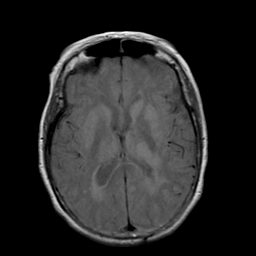

Stroke: proton density-weighted MR #2 -- Slice #13

[Home][Help][Clinical] Slice 13